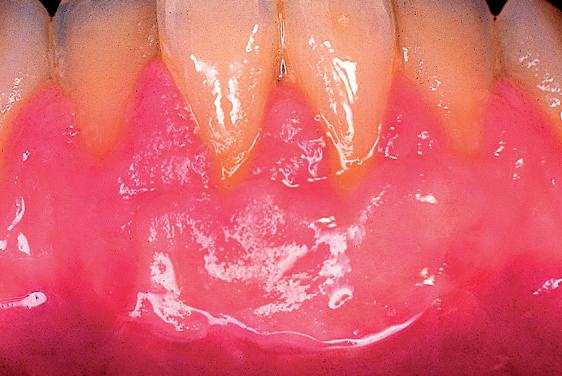

Lo que ocurre en este primer caso, al estar ya descrito en la literatura cientí ca, es el menos sorpresivo de los cuatro casos que se presentan. Sin embargo, no por ello deja de ser un fenómeno, en mi opinión, llamativo. Para interpretarlo correctamente, nos tenemos que situar a principios de la década de los noventa. La paciente S. G. de 26 años, desarrolló recesiones gingivales a nivel de 31 y 41 (Fig. 1). En aquella época, una de las técnicas quirúrgicas más frecuentemente empleada para el cubrimiento de las recesiones gingivales era el autoinjerto libre epitelizado, descrito por Holbrook y Oshenmbein en 1983.

Fig 1: Año 1990. Mujer de 26 años que presenta recesiones gingivales a nivel de 31-41.